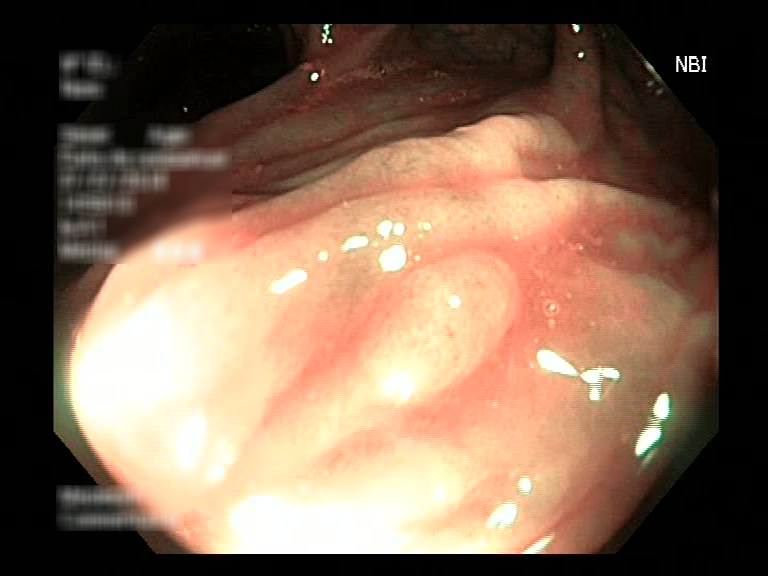

| Lesion | White Light Frame | NBI Frame | White Light Video | NBI Video | Camera Calibration |

| hyperplasic_01 |  |

|

WL.mp4 | NBI.mp4 | cam.xml |